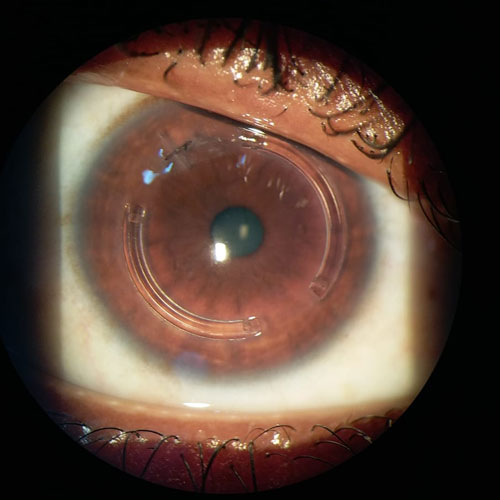

Dr. Abdul Rasheed, one of the leading Ophthalmologist and Cataract & Refractive surgeon in the city of Hyderabad provides extensive and comprehensive care for all your eye sight issues. Vision disturbance are one of the few issues which have the capacity to completely disturb our daily life and activities. Correcting them in the right way to avoid further complications or risk is the motto of Dr. Abdul Rasheed. With age comes cataract, Dr.Rasheed is an expert in complicated cataracts such as small pupil, zonular dialysis, mature / Brunescent cataracts, corneal scars, shallow Ac, etc., as well as complicated refractive surgery cases like RK scars, corneal scars, etc. While coming to refractive surgeries, Dr. Abdul Rasheed strongly believes and says "Any patient irrespective of complexity, who can be refracted to 6/6 can be treated to read the same without glasses." He has treated many patients of keratoconus who had extreme distortion of vision. After INTACS implantation followed by ICL, patients were able to regain normal vision.